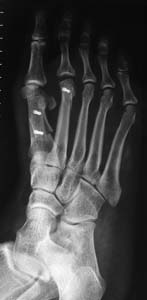

This is the x-ray finding:

A scarf osteotomy was performed. It involved cutting the 1st metatarsal bone using a Z-cut and displacing the toe laterally.